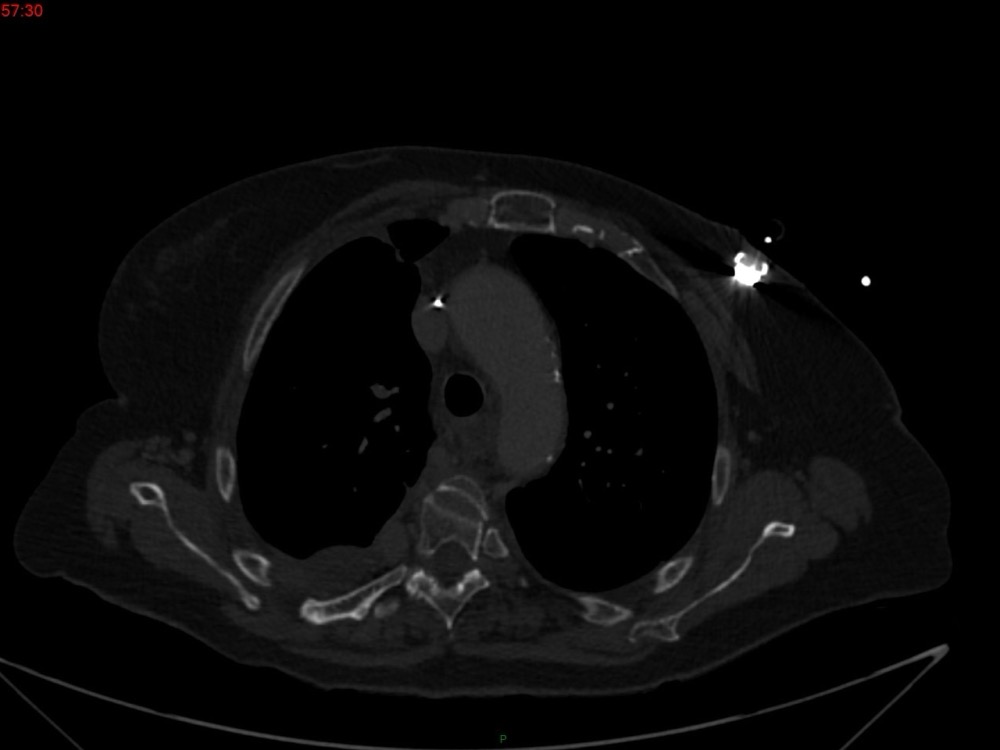

Marie Pauline Talabard 11/01/2023